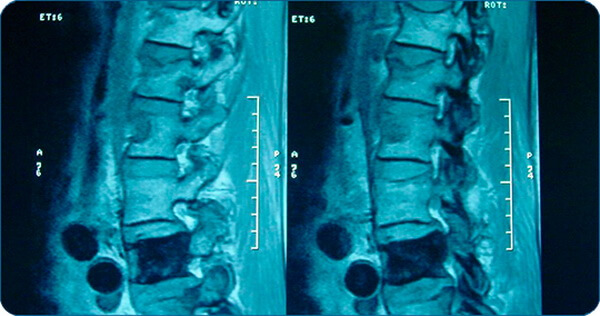

- во время диагностических исследований методом магнито-резонансной томографии. Этот метод позволяет не только обнаружить эностоз, но и определить его форму, состав.

Эностоз (костный островок) – это доброкачественное поражение кости обычно являющееся случайной находкой. Представляет собой небольшой фокус компактной губчатой кости. Его размер обычно не превышает 2 см. Состояние, при котором возникает множество костных островков, называется остеопойкилозом.

Что такое очаг эностоза?

Эностоз представляет собой округлый или овальный гомогенный очаг с признаками кортикального слоя (плотного вещества) кости. Размер обычно не превышает 1 см, но бывают гигантские образования.